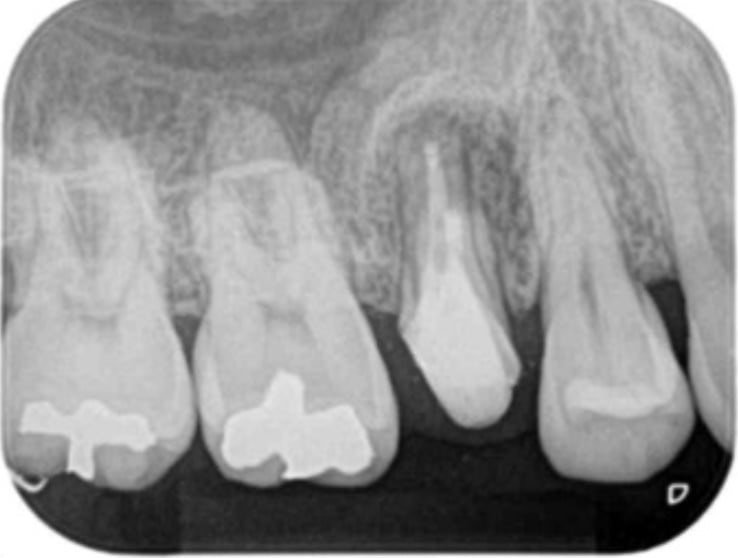

術前(深いむし歯)

術後(神経の一部を切除し特殊な材料で封鎖)

歯髄(歯の神経)の診断は非常に難しく、神経の状態を単純に評価することは不可能です。色々な診査を行い総合的に検討し「神経を残せるか?・残せないか?」を判断して意思決定します。この診査・診断・意思決定のプロセスは専門的な知識や経験が必要なので術者で差が出る部分になります。